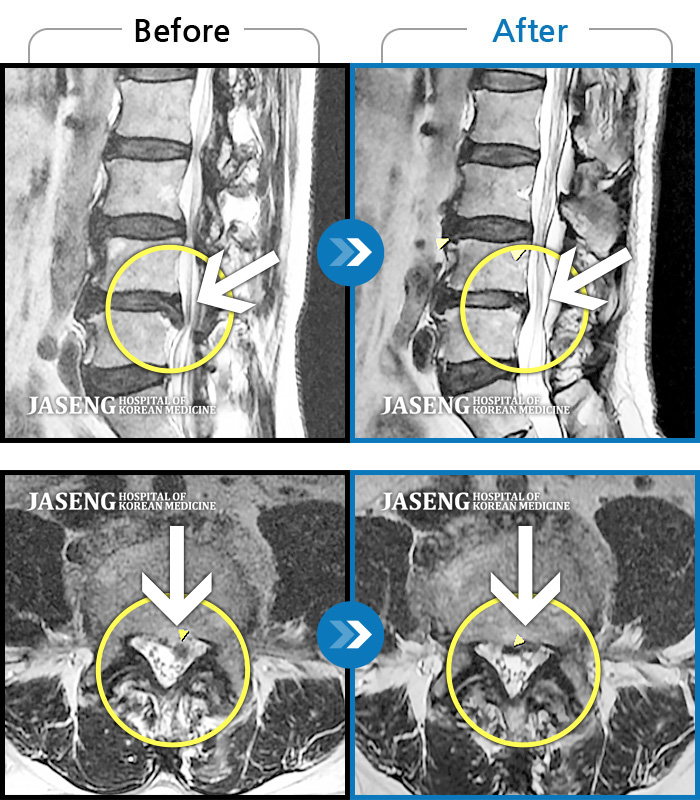

원재균원장님을 칭찬합니다 추간판탈출증으로 입원해서 치료 받는동안 항상 밝은모습 으로 허리와다리 통증있는 부분을 친절하게 설명해주시고 걱정해주셔서 너무 감사합니다 원장님의 극진한 치료 덕분에 좋은결과로 퇴원하게 되었습니다 감사합니다^~^

저는 허리디스크 파열로 자생한방병원에 입원하게 되었습니다 저를 치료해주시는 원장님은 원재균원장님이시구요 원장님은 항상 환자와 소통하기를 원하셔서 환자의 아픈부분 부분을 세세히 물어보시고 정성으로 치료해주시는 분입니다 침을 놓으실때도 꼼꼼히 정확하게 놓으시고 환자의 상태를 살펴주심니다 진료하실때 원재균원장님께서는 환자에게 도움을 주시려는 진심이 느껴졌습니다 진료를 마치고 회진을 도실때도 겉치레가 아진 진심으로 환자를 대하시고 스트레칭 방법이나 병원에서의 운동방법등을 세세히 설명해주셨습니다 저에게는 많은 도움이 되었구요 원재균 원장님 감사했고 고마웠습니다 항상 건강하십시요

저는 디스크 파열로 자생한방병원에 입원하게 되었습니다 감사하게도 원재균원장님의 진료를 받게되었구요 원장선생님은 다정다감하시고 환자의 말에 귀를 기울이셔서 어떻게 치료할까를 많이 생각하시고 침술을 배푸실때도 정성을 다하고 꼼꼼히 하시는 모습에 너무 감사했습니다 저녁 회진때도 형식적이 아닌 진심으로 한마디라도 환자에 보탬이 되게 말씀해주시는것 같았습니다 그말씀 듣고 스트레칭도 하고 치료를 받으니 정말 놀랍게도 상태가 많이 호전되어 퇴원하게 되었습니다 선생님 치료받는 동안 너무 감사했고 고마웠습니다 항상 건강하십시요^^